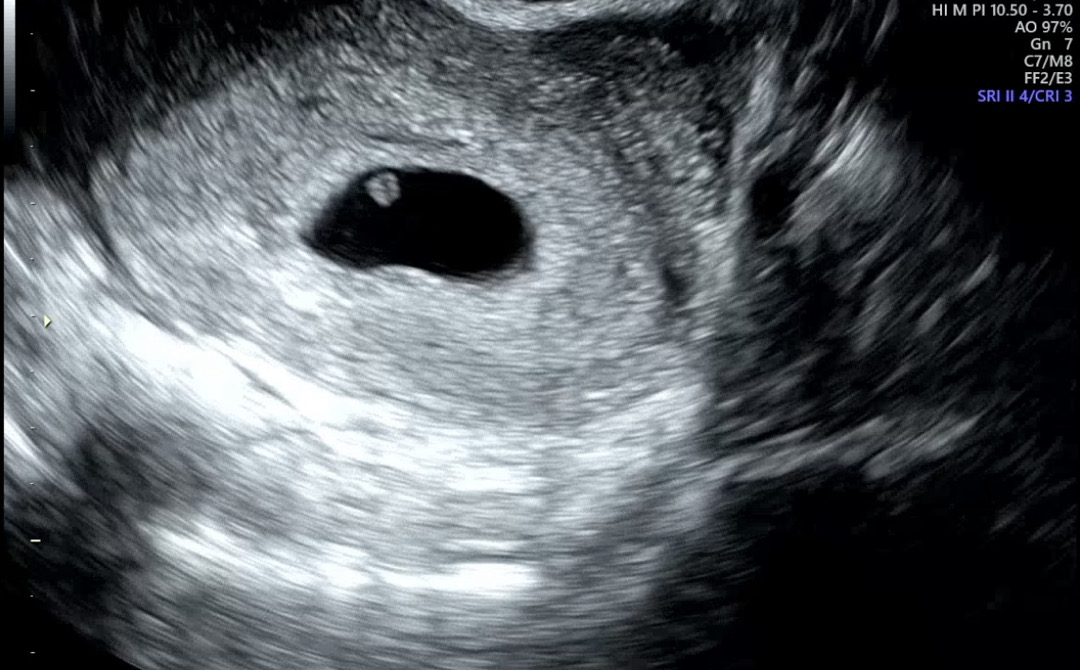

아기집과 난황은 보이는데 아기가 안보여요

막생과 관계 없이, 배란 & 착상이 모두 늦은 것 같다 하여 5주 말~6주 초로 추정하고 있는데요 오늘 초음파 봤는데 아기가 안보인대요 다음주 다시 보러 가기로 했는데 그때도 안보이면 쉽지 않을 것 같다고 하시네요 ㅠㅠ 같은 경험 있으신가요..! 흑